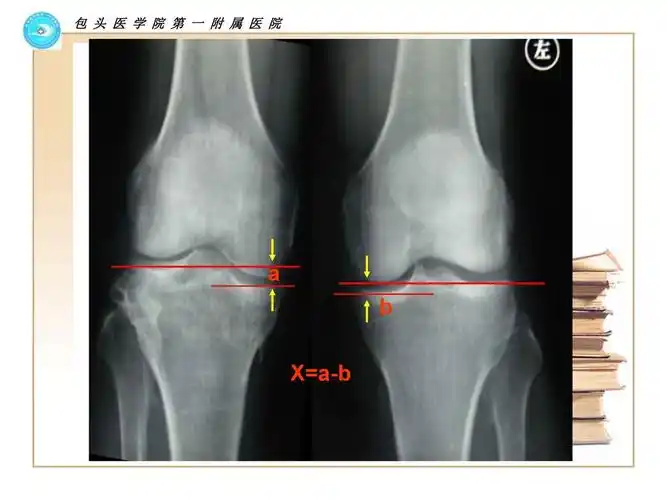

胫骨平台骨折术后平台高度丢失的原因分析与对策 田文平 董乐乐